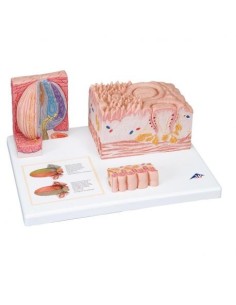

Des modèles anatomiques détaillés pour tous les besoins

Du crâne en 22 parties à verrouillage magnétique aux modèles de colonne vertébrale, des modèles d'articulation aux modèles de cœur, chaque pièce de notre collection est conçue pour une immersion totale dans l'étude de l'anatomie humaine. Nos modèles, réalisés à partir de scans d'os réels, garantissent une expérience tactile authentique et une fidélité de poids presque identique aux originaux.

Des outils pédagogiques innovants pour l'enseignement et la pratique de la médecine

Indispensables aux étudiants comme aux professionnels, nos modèles anatomiques sont des outils pédagogiques qui permettent d'observer les structures anatomiques avec précision, en évitant les dissections ou les études invasives. Ils sont également utiles pour expliquer les pathologies aux patients, ce qui rend la communication plus efficace et permet de gagner un temps précieux.